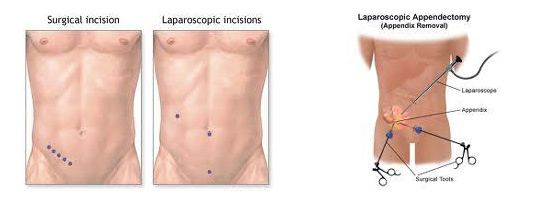

Στις περισσότερες λαπαροσκοπικές σκωληκοειδεκτομές, οι χειρουργοί χειρουργούν μέσα από 3 μικρές τομές (5 mm έως 12mm)

Χρησιμοποιώντας ένα σκληρό πλαστικό καθετήρα (trocar), ο χειρουργός εισέρχεται στην κοιλιά δημιουργώντας πνευμοπεριτόναιο. Έπειτα ένα λαπαροσκόπιο, (μικροσκοπικό τηλεσκόπιο συνδεδεμένο με μία βιντεοκάμερα) εισάγεται μέσω του trocar , δίνοντας στο χειρουργό μία μεγεθυμένη εικόνα των εσωτερικών οργάνων του ασθενούς σε μια οθόνη τηλεόρασης. Μέσω άλλων trocars ο χειρουργός χειρουργεί και αφαιρεί την φλεγμονώδη σκωληκοειδή απόφυση. Η όλη διαδικασία μπορεί να ολοκληρωθεί μέσα από τα trocars ή με επιμήκυνση σε μία από τις μικρές τομές για την είσοδο των trocars.